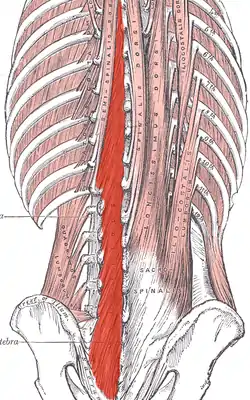

Deep muscles of the back. (Multifidus shaded in red.) | |

The multifidus (multifidus spinae : pl. multifidi ) muscle consists of a number of fleshy and tendinous fasciculi, which fill up the groove on either side of the spinous processes of the vertebrae, from the sacrum to the axis. While very thin, the multifidus muscle plays an important role in stabilizing the joints within the spine. The multifidus is one of the transversospinales.

Located just superficially to the spine itself, the multifidus muscle spans three joint segments and works to stabilize these joints at each level.

These fasciculi arise:

- in the sacral region: from the back of the sacrum, as low as the fourth sacral foramen, from the aponeurosis of origin of the sacrospinalis, from the medial surface of the posterior superior iliac spine, and from the posterior sacroiliac ligaments.

- in the lumbar region: from all the mamillary processes.

- in the thoracic region: from all the transverse processes.

- in the cervical region: from the articular processes of the lower four vertebrae.

Each fasciculus, passing obliquely upward and medially, is inserted into the whole length of the spinous process of one of the vertebræ above.

These fasciculi vary in length: the most superficial, the longest, pass from one vertebra to the third or fourth above; those next in order run from one vertebra to the second or third above; while the deepest connect two adjacent vertebrae.

The multifidus lies deep relative to the spinal erectors, transverse abdominis, abdominal internal oblique muscle and abdominal external oblique muscle.